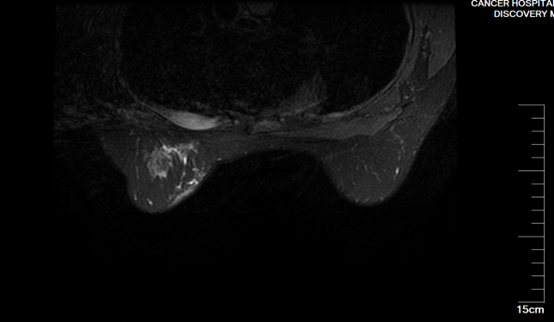

3、单孔腔镜腋窝淋巴结清扫术

微信图片_20221202184239.png

手术病例均为女性,年龄在50-62岁之间,左侧、右侧各1例,均在外院行腋窝淋巴结活检术证实转移,本次手术切口位置均选择隐蔽在腋窝皮肤皱襞,长度约2.5cm,清扫淋巴结数目15-22枚。

微信图片_20221202184225.jpg